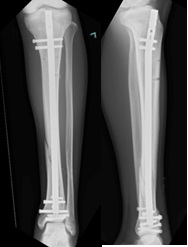

当センターは、救急救命センターを有する基幹病院の整形外科部門として、四肢・骨盤外傷に対する高度急性期医療と再建医療を担っています。高エネルギー外傷、多発外傷、開放骨折、骨盤骨折などの重度外傷を含む幅広い症例に対応し、迅速かつ的確な診断・治療を行っています。さらに、急性期治療にとどまらず、偽関節、変形治癒、骨欠損、重度軟部組織損傷に対する再建医療まで一貫した専門診療を行い、患肢機能の温存・再建と早期の社会復帰を見据えた質の高い医療を提供します。

- 四肢開放骨折

| 脛骨骨幹部骨折に対する髄内釘固定による日本の標準的治療: 多機関共同 後ろ向き コホート研究 |

山下伸之輔 | |